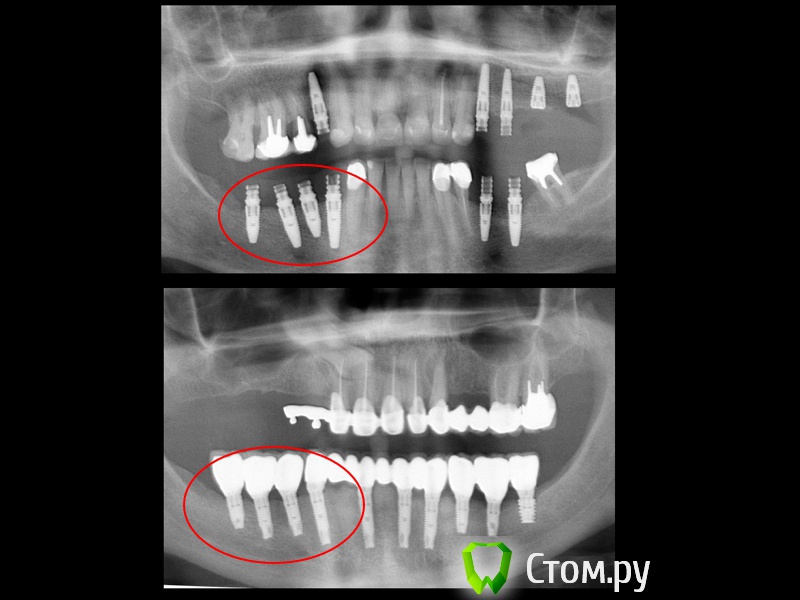

Большой Зеленый Опубликовано 23 ноября, 2013 Поделиться Опубликовано 23 ноября, 2013 За качество фоток не пинайте пожалуйста .Сделаны прежним фотоаппартатом все кроме первой .Купил зеркалку ,но пока не нашел где у нее кнопка "шедевр" )) Спасибо Павлу(Маэстро) просвещает меня серого в фотографировании.http://s017.radikal.ru/i401/1504/8c/4dd330654c7e.jpg http://s019.radikal.ru/i628/1504/94/71a6763fde50.jpg http://s019.radikal.ru/i629/1504/10/e162ee52831f.jpg http://s008.radikal.ru/i304/1504/70/fa915322dffa.jpg http://s017.radikal.ru/i437/1504/26/d17c6ca28d0a.jpg http://s018.radikal.ru/i500/1504/1a/a9571c622d4a.jpg http://s020.radikal.ru/i701/1504/04/36cc8cca1670.jpg http://s003.radikal.ru/i202/1504/69/49ae5a8aa44d.jpg 6 Ссылка на комментарий

red_butler Опубликовано 23 ноября, 2013 Поделиться Опубликовано 23 ноября, 2013 (изменено) А почему в пациентском? Это астра? Изменено 23 ноября, 2013 пользователем red_butler 1 1 Ссылка на комментарий

Большой Зеленый Опубликовано 23 ноября, 2013 Автор Поделиться Опубликовано 23 ноября, 2013 А почему в пациентском? Это астра?Перенес. Нет Это Нико Ссылка на комментарий

red_butler Опубликовано 23 ноября, 2013 Поделиться Опубликовано 23 ноября, 2013 Большой Зеленый, а почему так выбраны позиции? Ссылка на комментарий

Большой Зеленый Опубликовано 23 ноября, 2013 Автор Поделиться Опубликовано 23 ноября, 2013 Большой Зеленый, а почему так выбраны позиции? Был печальный опыт установки импланта с упором в верхушку 33 . (здесь на форуме тоже было пара случаев) Теперь такая философия. Ссылка на комментарий

komar56 Опубликовано 23 ноября, 2013 Поделиться Опубликовано 23 ноября, 2013 Прям ровненько стоят! Ссылка на комментарий

pit Опубликовано 23 ноября, 2013 Поделиться Опубликовано 23 ноября, 2013 Был печальный опыт установки импланта с упором в верхушку 33 . (здесь на форуме тоже было пара случаев) Теперь такая философия.В области 35, 45 зубов приключений больше. У тебя дистальный наклон имплантов в 4 секторе. Надо себя контролировать и упоров не будет. У меня периодически такие проблемы тоже бывают, причем на ровном месте (((( Ссылка на комментарий

red_butler Опубликовано 23 ноября, 2013 Поделиться Опубликовано 23 ноября, 2013 У нас обязательной частью протокола являются снимки с пинами параллельности, не раз выручали Ссылка на комментарий

pit Опубликовано 23 ноября, 2013 Поделиться Опубликовано 23 ноября, 2013 вроде не критично )Да вообще норм. Но в 3-м секторе дистальный наклон имеется. Ссылка на комментарий

pawa Опубликовано 23 ноября, 2013 Поделиться Опубликовано 23 ноября, 2013 46,47 шейки имплантатов не в кости? Ссылка на комментарий

Большой Зеленый Опубликовано 23 ноября, 2013 Автор Поделиться Опубликовано 23 ноября, 2013 46,47 шейки имплантатов не в кости?В кости. Ссылка на комментарий